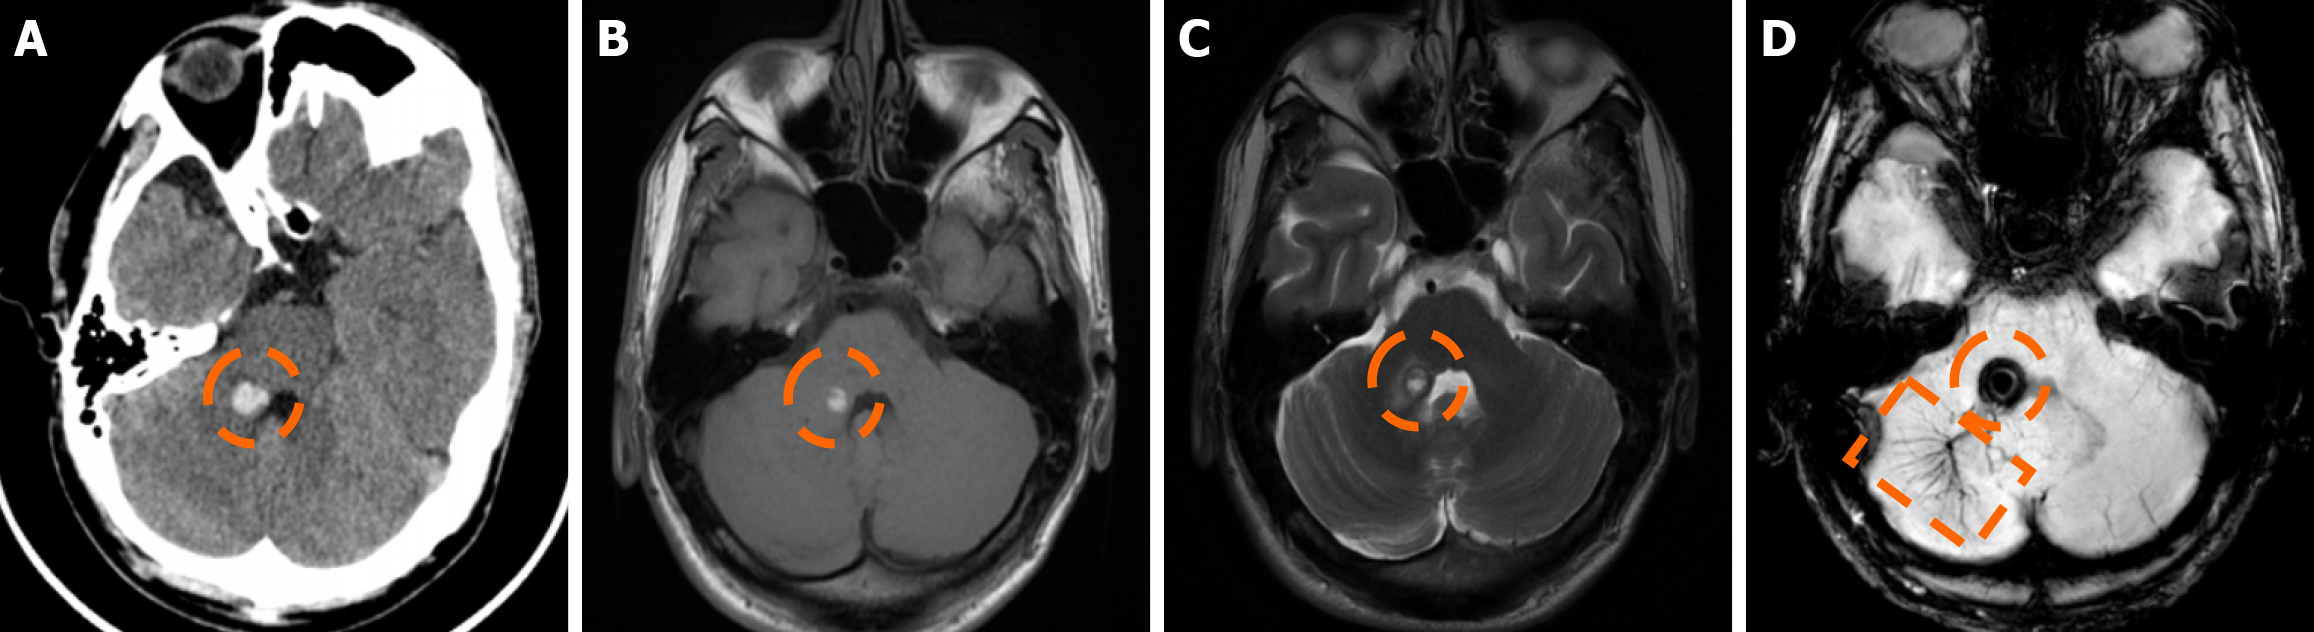

Imaging findings in coexistent DVAs and CMs will be the combination of those described for each malformation separately. Awareness of the possibility of their coexistence may prove invaluable in clinical practice. This is because recognition of a DVA close to a brain hemorrhage may raise suspicion for an underlying CM as the most likely etiology. Additional examinations and follow-up imaging following hematoma resolution will further enhance diagnostic confidence. Figures 8, 9, 10 and 11 illustrate clinical examples in which identifying the synchronous presence of a DVA adjacent to a brain hemorrhage (or suspected brain hemorrhage) enabled the diagnosis of a probable underlying CM as the most likely etiology, thereby avoiding unnecessary examinations or interventions.

The clinical applicability of the Zabramski classification is still being investigated. A retrospective cohort study evaluating the imaging evolution and clinical trajectory of 255 untreated patients with sporadic CMs over a follow-up period of approximately five years provided evidence that the Zabramski classification may facilitate risk stratification and contribute to treatment planning, particularly in determining the necessity for surgical intervention[89]. Furthermore, a recent study by Saari et al[88] established an association between the radiological characteristics of the Zabramski classification and their clinical relevance, emphasizing that type I lesions have a higher likelihood of becoming symptomatic. Nikoubashman et al[90] suggested an additional category (type V lesions) accounting for cavernomas presenting with gross extralesional hemorrhage. Various examples of CMs on CTs and MRIs, including familial cerebral CM cases, are shown in Figures 4, 5 and 6.